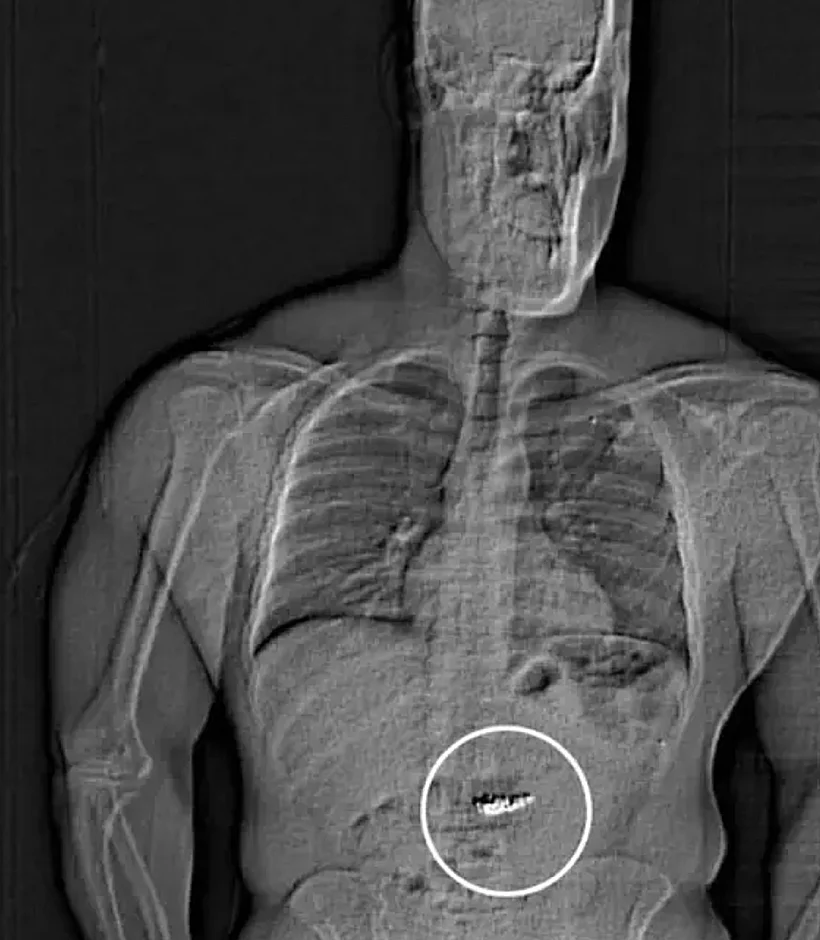

התכשיטים התגלו לאחר שגילדר שאל פתאום את הסוהרים בתא המעצר אם הוא יואשם בנוגע ל-״מה שיש לי בבטן״. פליטת הפה הזו שכנעה את החוקרים לערוך בו סריקת גוף שחשפה חפצים זרים במערכת העיכול שלו.

השוטרים חשדו כי החפצים הזרים הללו העגילים הגנובים, אך כדי לקבוע זאת הם נאלצו להמתין עד שהם יצאו מגופו של גילדר בדרך הטבעית.